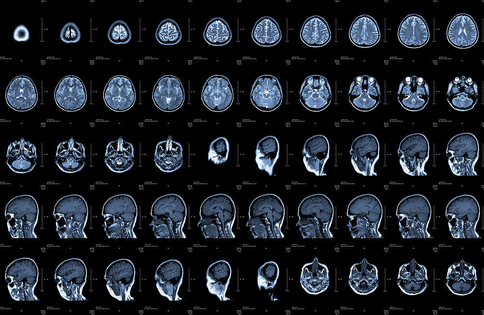

核磁共振:摇一摇再看。简单说就相当于摇一摇,让身体里的水分子振动起来,再平静下来,通过里面的振动来判断病灶。检查颈椎腰椎时,最佳选择是核磁共振。关节、肌肉、脂肪组织检查也可首选核磁共振。